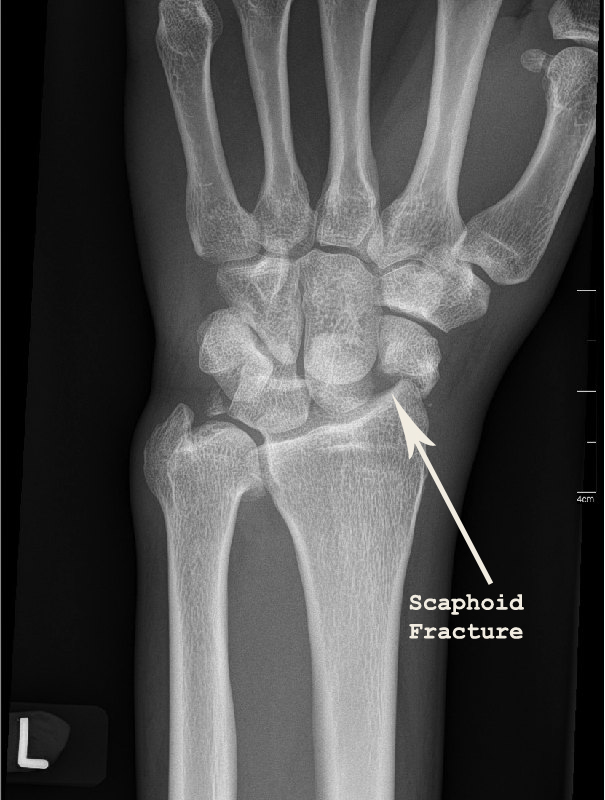

X-rays of his left wrist showed a fracture through the scaphoid bone of the wrist together with dislocation of the lunate bone. The diagnosis was a trans-scaphoid peri-lunate fracture dislocation.